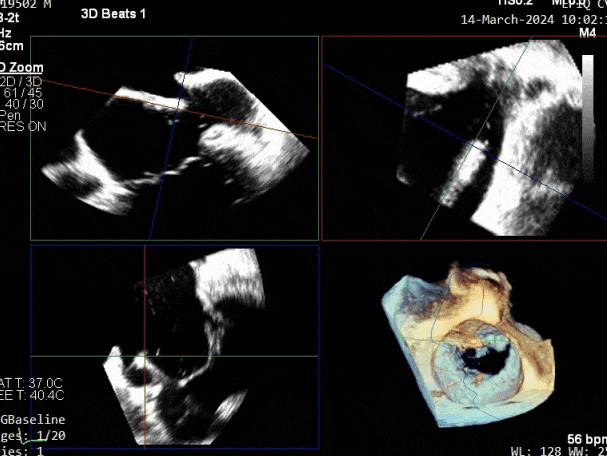

瓣膜夹释放前评估,二尖瓣反流减轻

瓣膜夹释放前评估,二尖瓣平均跨瓣压差及瓣口面积

释放瓣膜夹后评估,二尖瓣呈双孔,外侧仍有残余反流

第二个瓣膜夹进入左房,调整位置及方向,紧邻第一个夹子外侧

第二个瓣膜夹送入左心室,托住前后瓣叶,放下Gripper抓捕瓣叶

缓慢关闭第二个瓣膜夹

第二个瓣膜夹释放前评估,二尖瓣反流减轻

第二个瓣膜夹释放前评估,二尖瓣平均跨瓣压差及瓣口面积